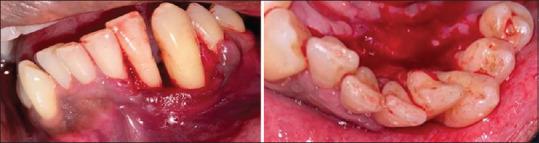

Fibrosarcoma is a rare malignancy of fibroblasts that seldom occurs in the oral cavity. Although rare, fibrosarcoma is an aggressive lesion associated with a poor survival rate. The occurrence of such a highly aggressive lesion on the gingiva is a diagnostic challenge for the clinician. This is because the gingiva is a common site for various inflammatory and nonspecific enlargements, which are commonly benign and the chances to overlook aggressive lesions are high. This case report describes an atypical case of fibrosarcoma of gingiva in a middle-aged individual that mimicked a nonspecific gingival enlargement.

纤维肉瘤是一种罕见的成纤维细胞恶性肿瘤,很少发生于口腔。尽管罕见,但纤维肉瘤是一种侵袭性病变,生存率较低。牙龈出现这种高度侵袭性病变对临床医生来说是一个诊断挑战。这是因为牙龈是各种炎症和非特异性增生的常见部位,这些通常是良性的,因而忽视侵袭性病变的可能性很大。本病例报告描述了一名中年个体牙龈纤维肉瘤的非典型病例,该病例酷似非特异性牙龈增生。